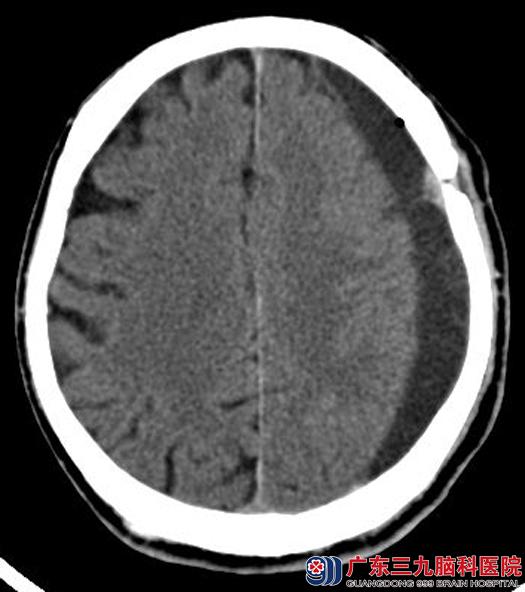

一周后行左侧额颞顶部慢性硬脑膜下血肿钻孔引流术,术中见陈旧性不溶液体流出,予冲洗至清亮。术后罗爷爷的头晕症状明显好转,已康复出院。

▲手术后